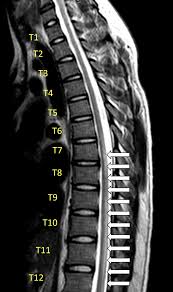

A fatty tissue called myelin protects these nerve fibers. Longitudinally extensive spinal cord lesions (lescl), also known as longitudinally extensive transverse myelitis (letm), represent extensive involvement of the spinal cord, with abnormal t2 signal traversing at least three vertebral body segments in length. Tm is characterized by weakness and numbness of the limbs. Transverse myelitis is not a single process but rather a syndrome with multiple causes. The spinal cord also carries sensory information back to the brain. It results from damage to nerve cells in a certain area. Transverse myelitis is an inflammation of your spinal cord. Transverse myelitis is typically characterized by subacute onset of motor weakness and sensory changes with or without bowel or bladder dysfunction. He has recovered and remains well. A spinal sensory level is usually detected on physical examination. Sagittal t2wi through the cervical spine demonstrates a longitudinally extensive segment of… Weakness, sensory disturbance, and autonomic dysfunction evolve over hours or days, most progressing to maximal clinical severity within 10 days of onset. Transverse myelitis (tm) is a rare neurological condition in which the spinal cord is inflamed.

Evaluation Of Idiopathic Transverse Myelitis Revealing Specific Myelopathy Diagnoses Neurology from n.neurology.org L'hermitte symptom (pain with forward neck flexion) may be present with cervical cord involvement. Transverse myelitis may occur in isolation or in the setting of another illness. The second mri showed a complete resolution of the cord swelling and patchy contrast enhancement. Idiopathic transverse myelitis is assumed to be the result of abnormal activation of the immune system against the spinal cord. Myelitis, is a collective term simply referring to any inflammation of the spinal cord. 1 article features images from this case A spinal sensory level is usually detected on physical examination. Longitudinally extensive spinal cord lesions (lescl), also known as longitudinally extensive transverse myelitis (letm), represent extensive involvement of the spinal cord, with abnormal t2 signal traversing at least three vertebral body segments in length.

Idiopathic transverse myelitis is a Longitudinally extensive transverse myelitis (letm) is a specific subtype of acute transverse myelitis that usually affects three or more vertebral levels and produces marked neurological deficits. Partial transverse myelitis and partial myelitis are terms sometimes used to specify inflammation that only affects part of the width of the spinal cord. Weakness, sensory disturbance, and autonomic dysfunction evolve over hours or days, most progressing to maximal clinical severity within 10 days of onset. Imaging studies of the spine ruled out an infective focus and no other lesions were seen within the cord. No significant medical history other than a mild upper respiratory infection a few weeks prior. Figure 93a figure 93b figure 93c findings figure 93a: Clinical and first mri were both favoring the diagnosis of transverse myelitis, after which the patient received corticosteroid treatment. Transverse myelitis (tm) is a rare neurological condition in which the spinal cord is inflamed. Tm is characterized by weakness and numbness of the limbs. Although any cord level can be affected, the classic description includes a preference for the thoracic cord 14. When it occurs without apparent underlying cause, it is referred to as idiopathic. Sagittal t2wi through the cervical spine demonstrates a longitudinally extensive segment of…